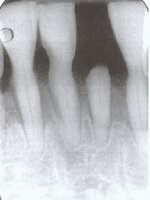

So sehen gesunde Zähne aus

Pro 15.jpg

und so welche, dier über einen längeren Zeitraum hinweg mit den falschen Instrumenten behandelt worden sind.

Pro 46.jpg